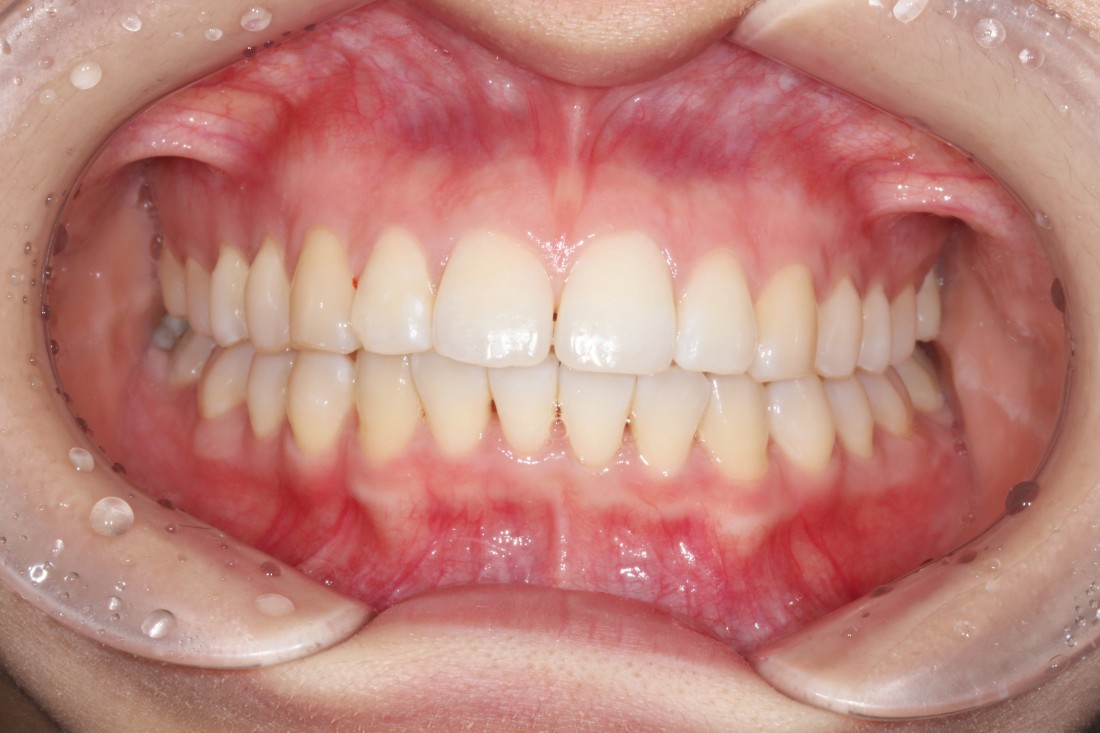

광주 교정치과

충치치료 + 치아교정 동시 케이스

광주 교정치과 추천하는 이유는

전문의 충치치료까지 동시에 가능하여

토탈 구강건강 관리를 받으실 수 있기 때문입니다.